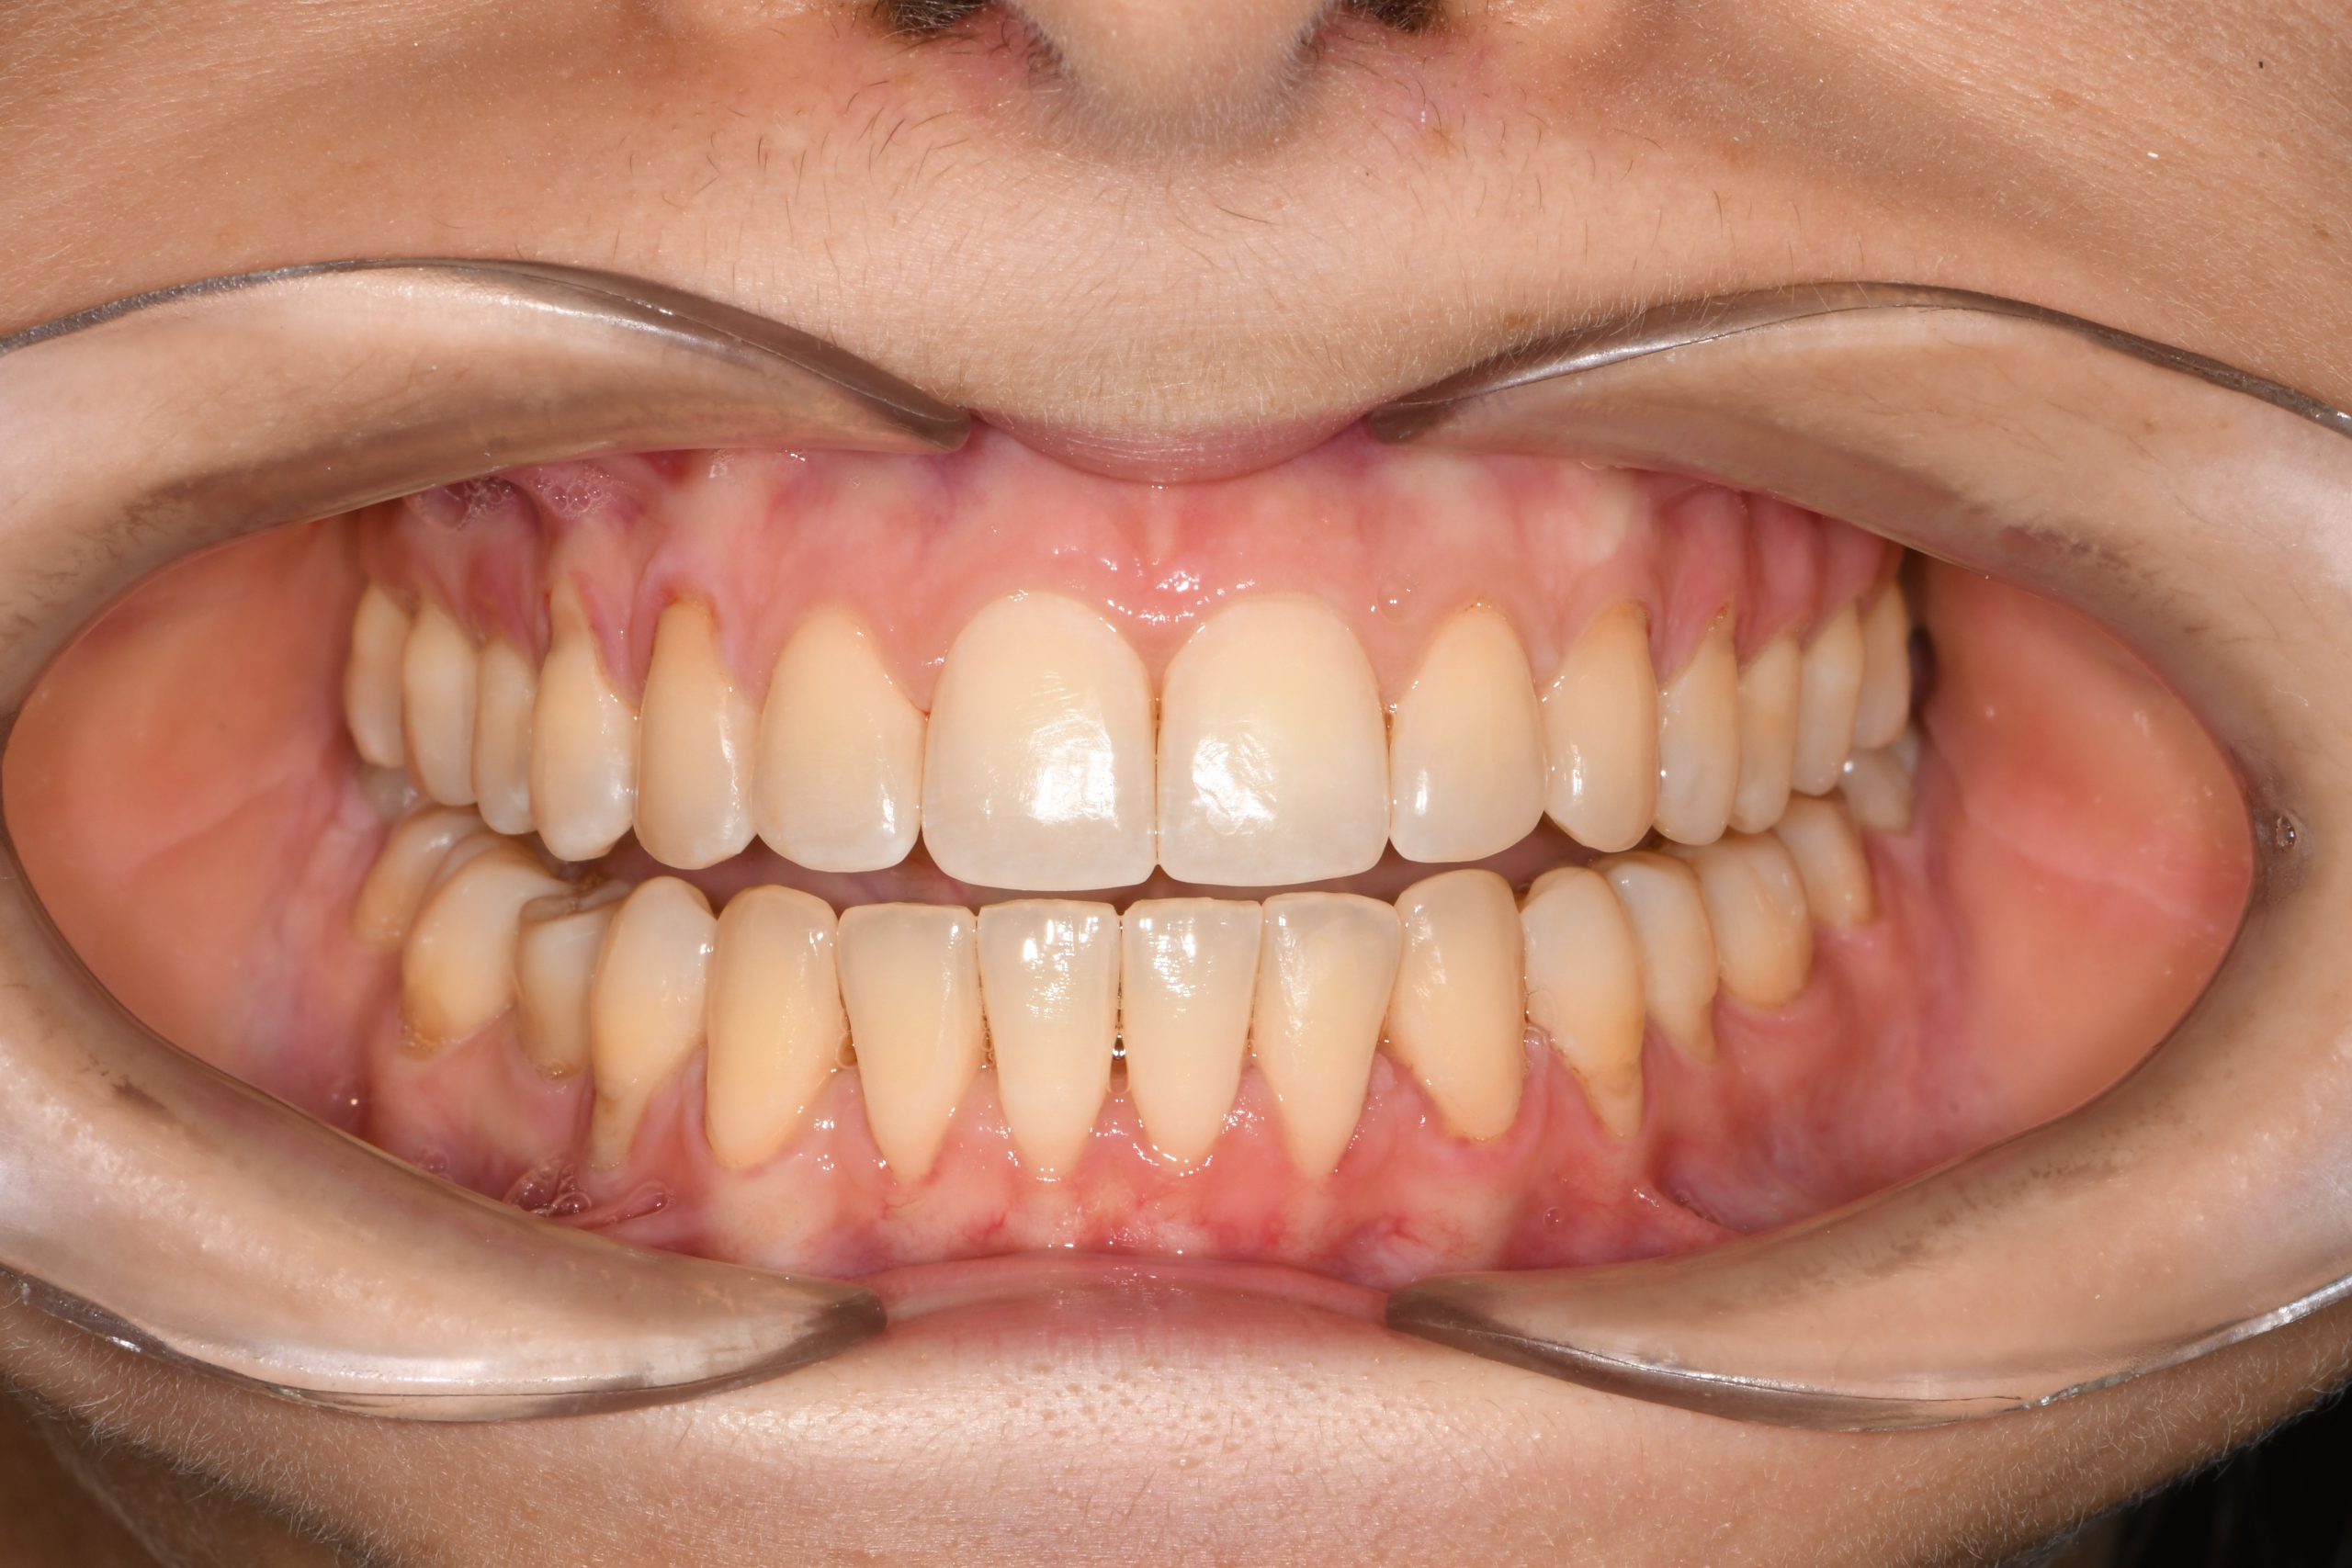

Az elmúlt évekből rengeteg szakmai referenciát tudnánk bemutatni, amelyek különböző fogszabályozási problémákat oldottak meg. Válogatva a több száz esetből, ezen az oldalon olyan képeket, információkat igyekeztünk bemutatni, amelyeknek a segítségével a jövőbeni pácienseinknek azt tudjuk üzenni: A Te fogsorod is lehet gyönyörű!

(Képeket a Pácienseink külön írásos beleegyezésével mutatjuk be!)